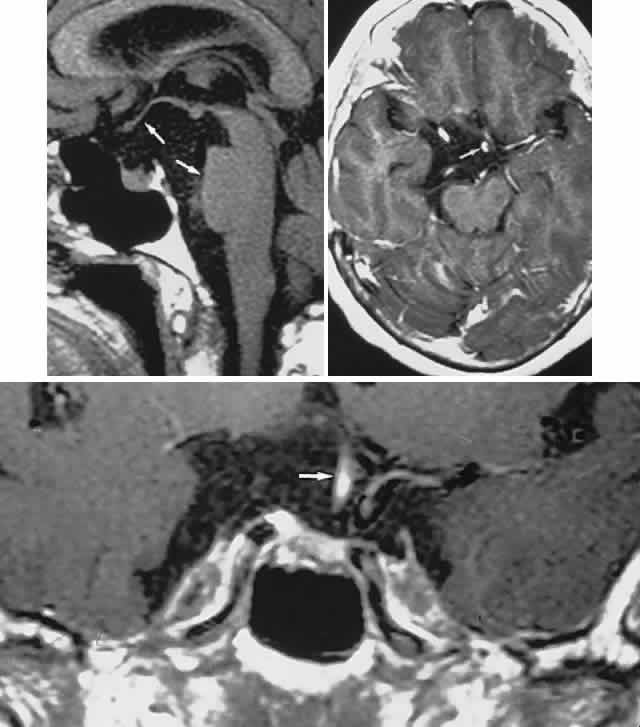

In previous decades, chiasmal interference with optic atrophy, but “normal” plain skull films, was referred to as “Cushing's syndrome of the chiasm,” caused by meningiomas, aneurysms, or other noncalcified suprasellar lesions. The modern neuroimaging techniques of enhanced CT, “bone-window” protocols, and gadolinium-contrasted MRI are now exceedingly sensitive in disclosing meningiomas or other parachiasmal masses (Fig. 4). At present, contrast-enhanced CT or MRI precisely demonstrate extra-axial tumor configuration; CT is superior in disclosing calcification or bone changes, but it is inferior for assessing suprasellar or intrasellar extension, postsurgical changes, and vascular displacement or encasement.76 Whether MRI or even MR angiography obviates standard selective arteriography, especially when surgical intervention is contemplated, is moot.

Fig. 4. Magnetic resonance imaging of a suprasellar meningioma (TR, 600 milliseconds; TE, 20 milliseconds). A. Coronal section of a large meningioma (large arrows), isodense to brain. B. Sagittal section. Note the normal sella and pituitary gland (p). Sagittal (C) and coronal (D) sections of a planum meningioma, extending into the sella. Note the upward deflection of the chiasm (arrow in C) and extension to the cavernous sinus (arrows in D).

CT scanning retains special relevance to craniopharyngioma diagnosis, currently superior to MRI in detection of calcification and cyst formation (Fig. 7A to C); however, the extent of involvement of adjacent structures, that is, the optic chiasm, third ventricle, and intracavernous carotid artery, is more clearly delineated by MRI (Fig. 7D and E).93 Craniopharyngioma fluid collections are found to be uniformly bright on T2-weighted sequences, but on T1-weighted images, the signal intensity may range from hypointense to hyperintense, reflecting the heterogeneous contents of cysts. Because calcification and cyst formation are hallmarks of craniopharyngiomas, CT is more specific than MRI. At times, intrinsic infiltration of tumor may thicken the chiasm and contiguous optic nerve, a radiologic configuration that mimics glioma.94 Likewise, glioma may be simulated when the optic canal is invaded and enlarged, but accompanying bony erosion of the sella weighs heavily toward craniopharyngioma.

Fig. 7. Computed tomography scan of a large, multicystic craniopharyngioma. A. Axial section through the sella shows destruction of the bony skull base. Axial (B) and coronal (C) sections show cysts (white arrows) and calcification (arrowheads). Contrast-enhanced magnetic resonance imaging of the craniopharyngioma. Sagittal (D) and coronal (E) sections with gadolinium show solid and cystic (arrows) portions.